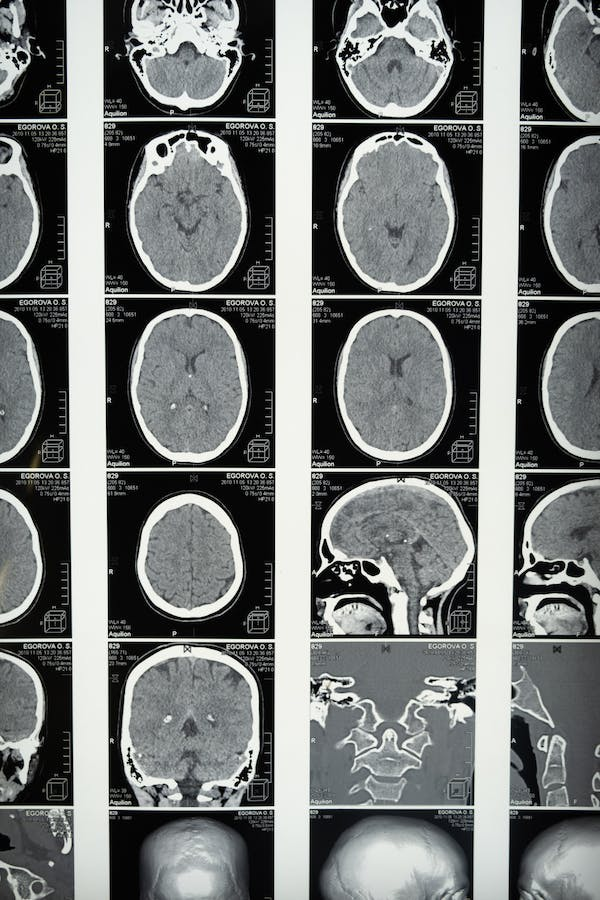

Como ha sido mencionado con anterioridad, se ha vinculado el dolor del miembro fantasma con cambios en la corteza somatosensorial cerebral y con la reorganización de la corteza motora a partir de la amputación. Lo que estaría vinculado a la intensidad y frecuencia del dolor experimentado.

Relacionado a ello, resulta relevante destacar que la visión se encuentra directamente relacionada a la percepción y el movimiento. Así, los teóricos de la terapia del espejo hipotetizan que esta podría influir significativamente en una nueva reorganización cortical.

En este sentido, se han realizado investigaciones de neuroimagen que sugieren que dichos cambios son posibles. Esto sucede especialmente en la organización cortical somatosensorial representativa del miembro amputado.

Además, a partir del entrenamiento frecuente con el espejo, se ha encontrado que la representación de ambos hemisferios cerebrales comienza a asimilarse, tomando el estado del hemisferio que no se encuentra disparando señales de dolor. Sin embargo, un gran porcentaje de personas no logran beneficiarse de dicha terapia. Y es que, a pesar de tales hallazgos, las condiciones de cada caso no son iguales y, por tanto, no siempre responden de forma similar a los tratamientos (Foell et al., 2013).